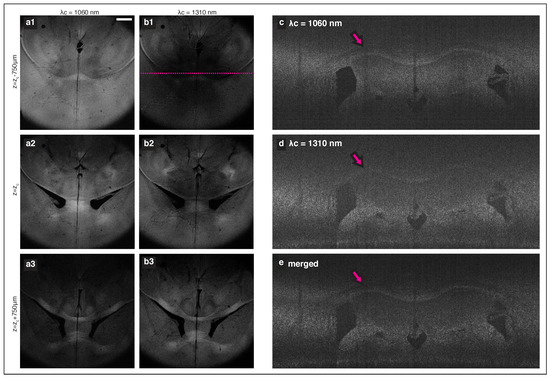

The focal shift between separate imaging bands may also be useful for volumetric imaging for samples that allow larger penetration depth such as lipid-cleared tissues. It has been demonstrated that the intact brain sample can be imaged at optical resolution with clearing assisted scattering tomography (CAST) [29], a method combining OCT with a controlled clearing of lipid. While the lipid removal can be optimized to provide sufficient contrast throughout the entire depth of the sample, the shallow DoF determined by the high NA objective lens mandates step-wise adjustment of the focal plane to enable the 3D imaging for a large volume. We examined application of the multi-band source in CAST. The murine brain tissue (from a wild type C57BL/6 mouse, aged 6–8 weeks) was prepared following a customized clearing method based on SWITCH [30] protocol. Before and during imaging, the sample was submerged in a refractive-index matching solution (23.5% ( w / v ) N-methyl-D-glucamine, 29.4% ( w / v ) diatrizoic acid, and 32.4% ( w / v ) iodixanol). In general, this solution aided in suppressing scattering and achieving adequate SNR. However, the absorption loss in the 1550 nm imaging spectrum was too large to obtain a meaningful contrast, and the imaging was only performed using the two shorter wavelength subsystems. The sample was placed with superior cortex facing the objective. A set of volumetric data was acquired from individual interferometers and processed independently with depth-scale matching. A set of 29 discrete end-face sections were obtained using MIP, over a range of 105 μ m for each plane. Figure 4a,b shows three selected examples of such MIP planes (horizontal cross-sections) that are 0.75 mm apart. The reduced collection efficiency due to the focal shift between imaging sources is apparent as individual sources capture different features along the depth. Figure 4c–e compares the OCT XY-tomogram (coronal section) of a single source (c) λ c = 1060 nm and (d) λ c = 1310 nm with the equivalent cross-section taken from the merged stack (using two bands).

Figure 4. Dual-band imaging results of cleared murine brain. (a,b) Sectional MIP of two horizontal planes that are 0.75 mm apart. Comparison of a coronal section taken from (c) the 1060 nm band, (d) the 1310 nm band, and (e) the merged stack. Tomograms in (ce) are taken at the line marked in (b1). The magenta arrows mark the corpus callosum, which is better captured by the 1060 nm system and therefore displayed with increased contrast in the merged tomogram.